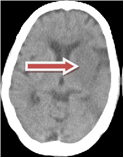

brainCT3 brainCT4

We have developed a unified method to detect both types of strokes from a given CT volume data. The proposed method is based on the observation that stroke presence disturbs the natural contra-lateral symmetry of a slice. Accordingly, we characterize stroke as a distortion between the two halves of the brain in terms of tissue density and texture distribution.